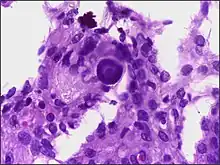

Micrograph of psammoma body in the centre of the field in a meningioma of brain. H&E stain.

Psammoma bodies usually have a laminar appearance, are circular, acellular and basophilic.